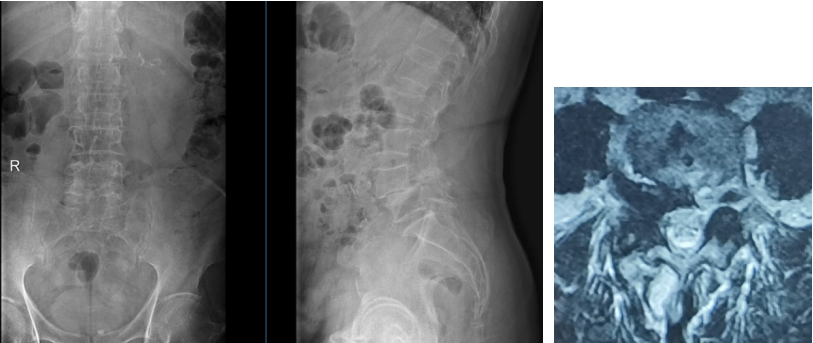

72岁的周先生,在4年前无明显诱因出现腰部酸胀不适,侧身时加重明显,伴右下肢麻木、疼痛,以右大腿后外侧、足跟较为明显,行走后加重,休息后可稍缓解。在当地医院行小针刀、针灸等对症治疗,症状稍有缓解,之后症状又反复发作。半年前症状加重,为求进一步诊治,在家人的陪同下慕名来到了海军军医大学附属长征医院脊柱外科许鹏教授处就诊。门诊腰椎MRI显示:1、腰4椎体向前I°滑脱,伴双侧峡部裂。2、腰椎退变,腰4/5、腰5/骶1椎间盘膨出,腰部皮下软组织肿胀。门诊遂以“腰椎滑脱症”收入院。

术前X片、CT、MRI